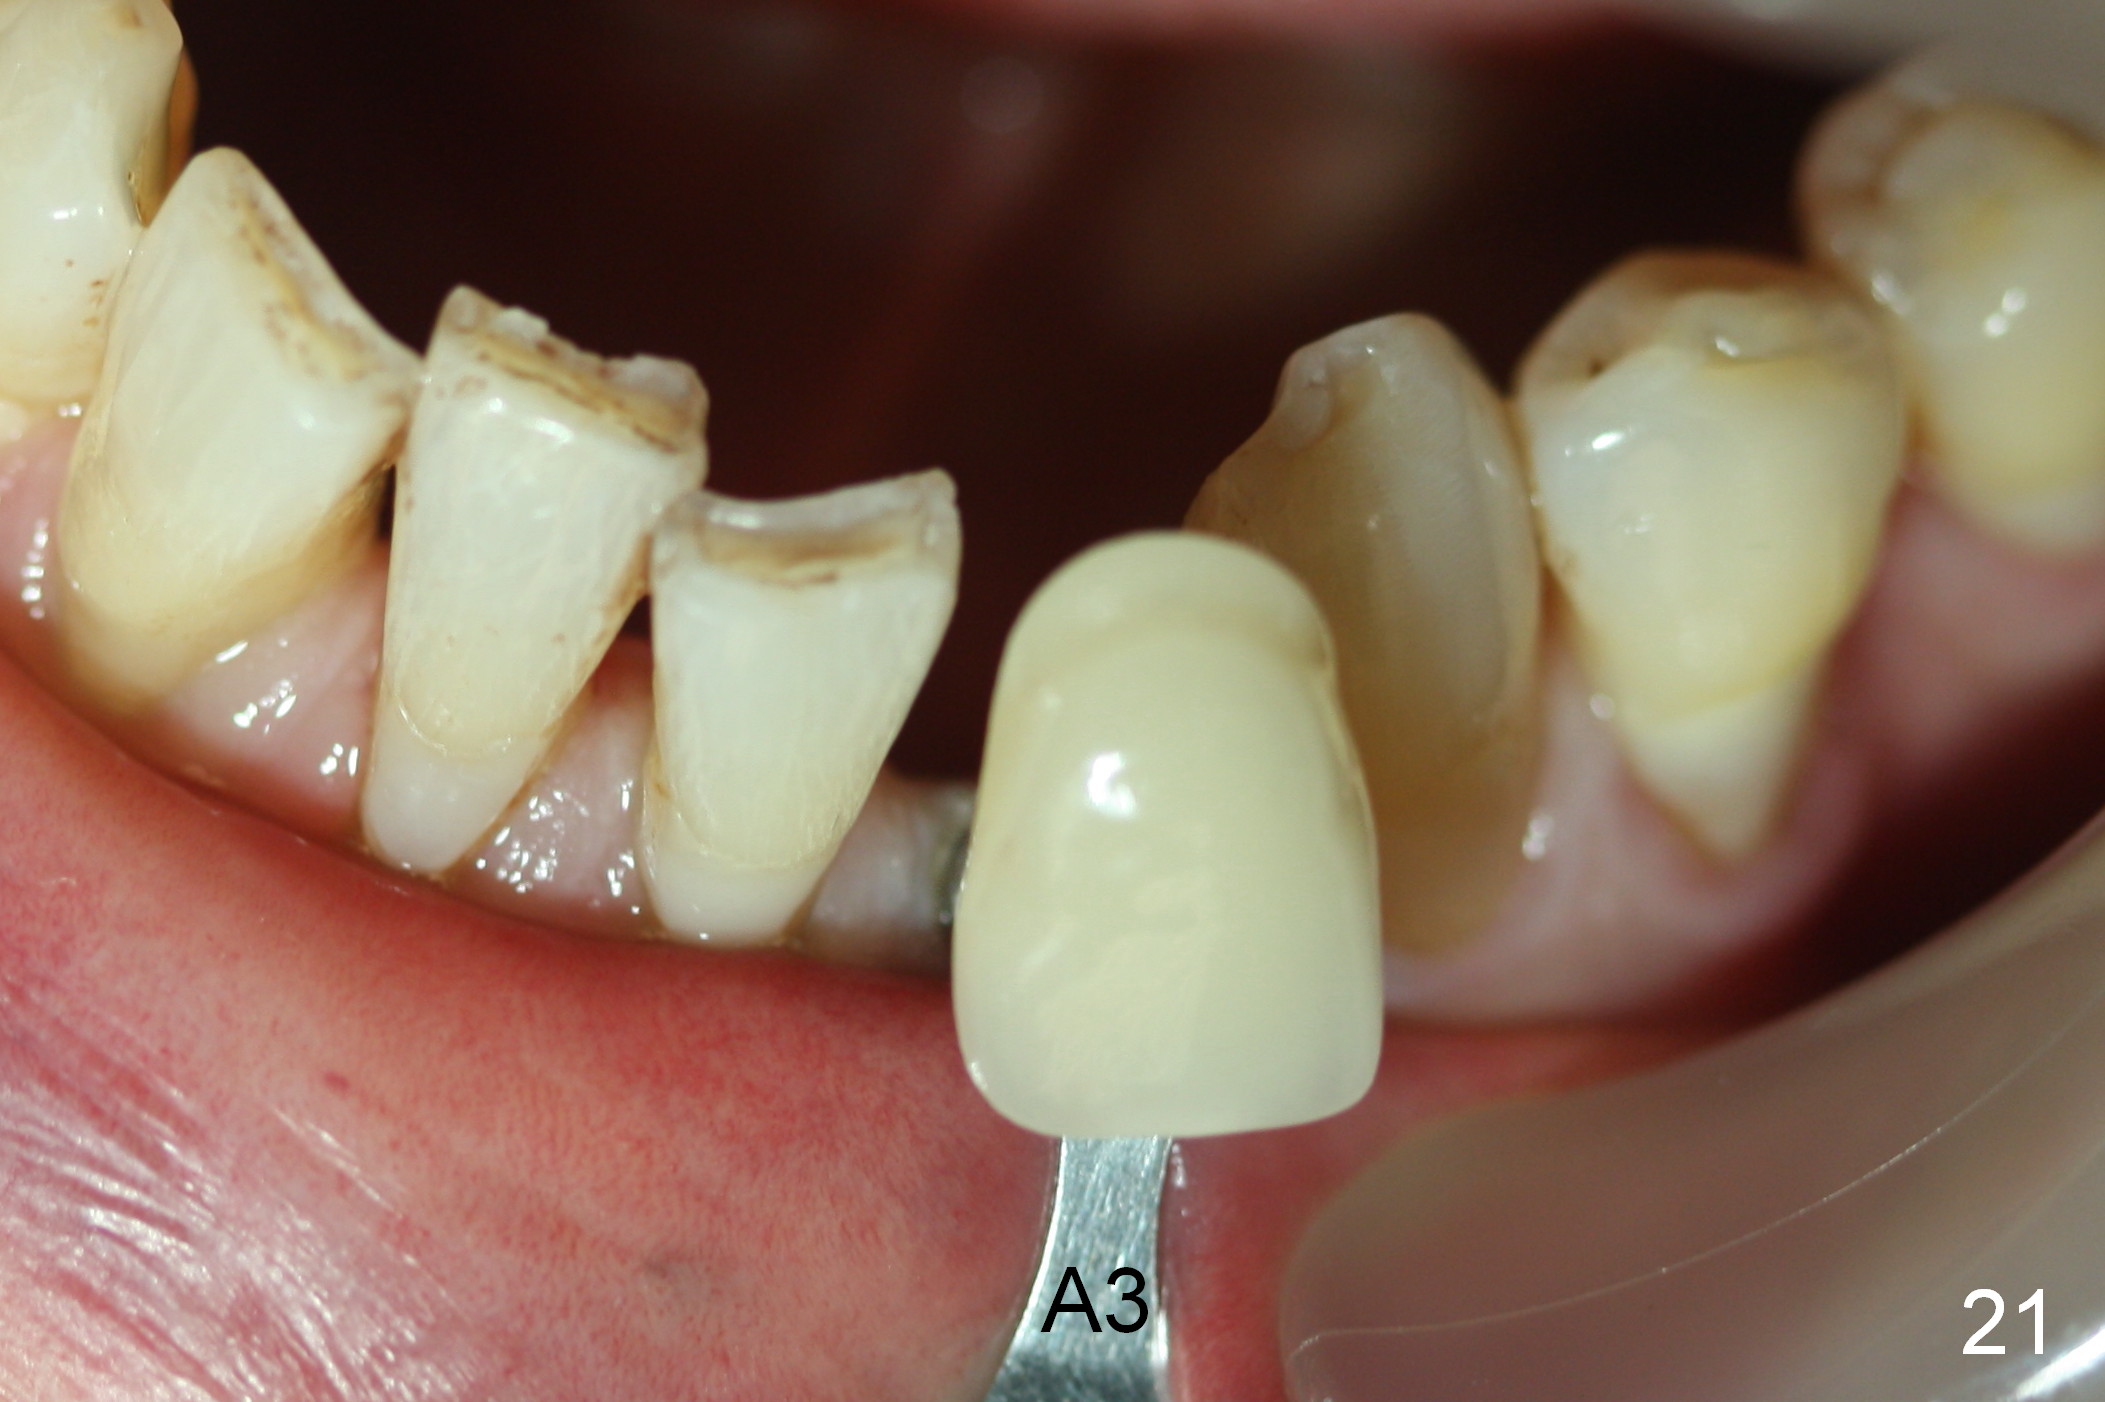

A 74-year-old man has several missing teeth (Fig.1).  His 1st goal is to replace the lower left lateral incisor (Fig.2).  The residual root has an apical lesion (Fig.3 *).  To describe intraop findings, a CT image of a different patient is used (Fig.4 coronal section; B: buccal; L: lingual).  After extraction, the buccal plate is found to be thin and low (Fig.5 arrowheads).  A 1.5 mm pilot drill (Fig.6 red line) is used to initiate osteotomy in the lingual plate of the socket.  Once the drill penetrates the lingual plate, the trajectory changes and the depth is 17 mm from the gingival margin (Fig.7).  A PA is taken (Fig.8); it appears that the osteotomy can be extended more apically.  When the pilot drill extends to 20 mm, there is sudden empty feeling.  The lingual plate has perforated (Fig.9).  A new osteotomy is established buccally (Fig.10 pink).  To avoid buccal plate perforation, especially in the buccal undercut area (>), the coronal end of the drill has to be tilted buccally (<--).  An angled abutment (3x20 mm, 15°) is placed (Fig.11,12).  The abutment is modified (Fig.13,14) to accommodate an immediate provisional (Fig.15,16 P).  Perio dressing is to be applied to prevent the bone graft from getting dislodged buccally (Fig.15).  The dressing is in place 7 days postop (Fig.17).

Five months postop, the peri-implant space reduces (Fig.18).  A keratinized band forms buccal to the implant (Fig.19 *).  The provisional dislodges probably due to the buccal placement (Fig.20).